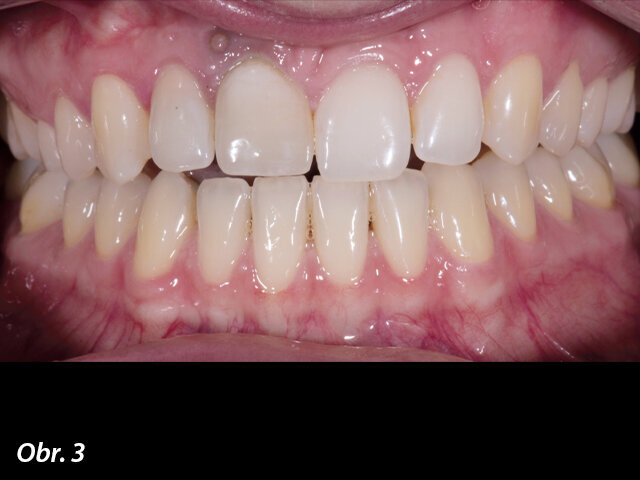

Po externí resorpci kořene měla mladá 28letá pacientka nenávratně poškozen zub 11. Byla zjištěna vestibulární píštěl a sekvence rentgenových snímků vykazovala progresivní poškození kořene, které zahrnovalo střední a cervikální třetinu kořene zubu (obr. 2–5).

Ve všech případech, kdy se jedná o estetiku, vždy provádím studii úsměvu podle konceptu DSD (Digital Smile Design) a snažím se optimalizovat harmonii mezi zuby pacienta a jeho tváří (obr. 6). I v případě, jako je zde prezentovaný, kdy je nutno ve frontálním úseku nahradit pouze jeden zub, tento přístup pomůže odhalit případné nesrovnalosti s ohledem na ideální situaci (obr. 7). Morfologie přirozeného zubu 21 byla proporcionálně vyhovující a harmonická ve vztahu k sousedním zubům – při zhotovení korunkové náhrady zubu 11 jsem se tedy omezil na zrcadlové kopírování zubu 21. Výsledný tvar korunkové náhrady zubu 11 se pak ukázal jako optimální pro oporu měkkých tkání a zachování jejich tvaru po zavedeném implantátu. Léčebný plán tedy zahrnoval chirurgický zákrok zavedení implantátu, okamžité zatížení zavedeného implantátu provizorní korunkovou náhradou a po vhojení implantátu zhotovení definitivní korunkové náhrady digitálním výrobním postupem.